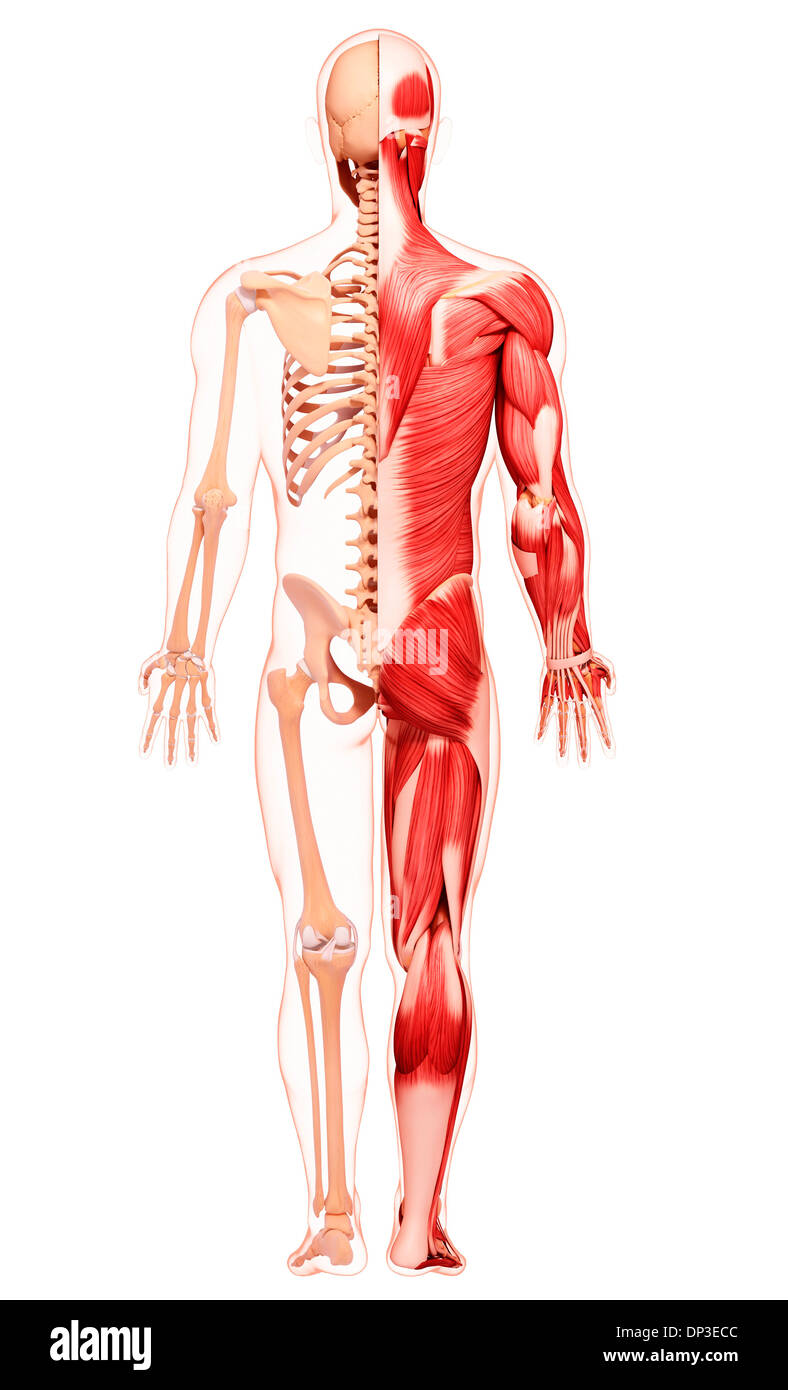

Les droits de l'Anatomy, artwork Banque D'Imageshttps://www.alamyimages.fr/image-license-details/?v=1https://www.alamyimages.fr/les-droits-de-l-anatomy-artwork-image65230716.html

Les droits de l'Anatomy, artwork Banque D'Imageshttps://www.alamyimages.fr/image-license-details/?v=1https://www.alamyimages.fr/les-droits-de-l-anatomy-artwork-image65230716.htmlRFDP3ECC–Les droits de l'Anatomy, artwork